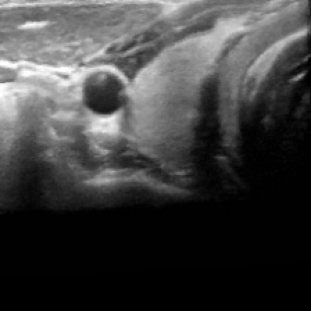

We propose a novel approach that adapts hierarchical vision foundation models for real-time ultrasound image segmentation. Existing ultrasound segmentation methods often struggle with adaptability to new tasks, relying on costly manual annotations, while real-time approaches generally fail to match state-of-the-art performance. To overcome these limitations, we introduce an adaptive framework that leverages the vision foundation model Hiera to extract multi-scale features, interleaved with DINOv2 representations to enhance visual expressiveness. These enriched features are then decoded to produce precise and robust segmentation. We conduct extensive evaluations on six public datasets and one in-house dataset, covering both cardiac and thyroid ultrasound segmentation. Experiments show that our approach outperforms state-of-the-art methods across multiple datasets and excels with limited supervision, surpassing nnUNet by over 20\% on average in the 1\% and 10\% data settings. Our method achieves $\sim$77 FPS inference speed with TensorRT on a single GPU, enabling real-time clinical applications.